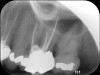

Clinical procedure: If apical bone loss is present (Figure 1) a collagen/gelatin sponge (eg, Gelfoam®, Pfizer Inc., www.pfizer.com) can be placed apically so that the MTA can be delivered to the desired working length. (Any other surgical resorbable sponge would also work, such as OraPlug® [Salvin Dental Specialties, www.salvin.com], Surgifoam® [Midwest Dental, www.mwdental.com], or Surgispon® [Aegis Lifesciences, www.surgispon.com]). This is done by taking a small piece (2 mm x 2 mm) of the resorbable sponge and pushing it down to and through the root apex with an endodontic file. Once this is done, MTA is packed down the canal with a custom-fitted cone. The clinician can use a rubber stopper on the gutta-percha cone to know the exact length of MTA placed in the apical third (Figure 2). Once the apical third is sealed with 3 mm to 5 mm of MTA, the remaining coronal canal space can be back-filled using a warm gutta-percha technique (Figure 3).